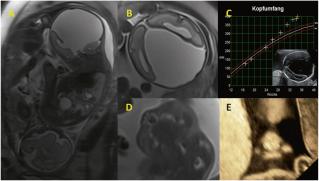

Interhemisphärische Hirnzyste (Autopsiebefund noch nicht vorliegend) im Rahmen eines komplexen, zerebralen Fehlbildungsmusters mit Balkenagenesie und im MRI auch Hinweise einer kortikalen Organisations- und Reifungsstörung v.a. der linken Hemisphäre mit Verminderung der Gyrierung. (Bilder A–C) Neben diesen schweren Fehlbildungen zusätzlich auch in der Diffusion nachweisbare, ischämische Schädigung des Kortex. Die Gesichtsanomalien (bilaterale Lippen-Kieferspalten und Gaumenspalte) konnten auch postnatal bestätigt werden. (Bild D: MRI/ Bild E: multiplanare 3D Sono) Im Verlaufe der Schwangerschaft hat die Zyste deutlich an Volumen zugenommen mit exponentiellem Wachstum des Kopfumfanges. (Bild C) Die Genetik war unauffällig.

Das Paar hat sich zum Austragen der Schwangerschaft entschieden mit der Option, das Kind palliativ zu betreuen. Mit 35 Wochen Eintritt wegen Blasensprung. In Anbetracht der Gesamtsituation und auch der Tatsache, dass der Kopfumfang nun bei 40 cm (!) angelangt war, wurde vor der Sectio eine ultraschallgesteuerte Punktion durchgeführt mit Aspiration von über 500 ml Flüssigkeit bis zu einem Kopfumfang von 34 cm. Das Kind ist kurz nach der Geburt in den Armen der Eltern verstorben. Dem Co-Zwilling ist es glücklicherweise gut ergangen.